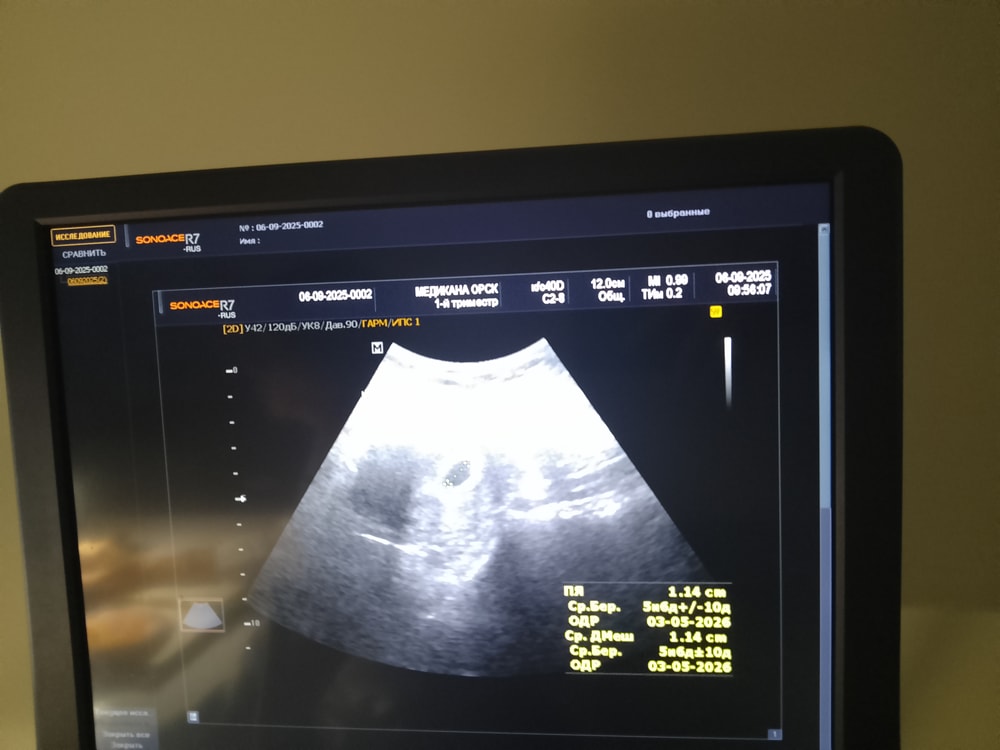

Вы госпитализированы? Гематома большая, эмбриона не видно, но шанс ещё есть, на мой взгляд.

Татьяна, нет, у нас никто не положит с гематомой, тем более на учете не стою, ставят только с 9 недель, репродуктолог сказала просто ждать неделю следующего УЗИ. Это считается большой гематомой? Врач с перинатального сказала, что маленькая совсем

anna10082018, посмотрите на размер вашего плодного яйца и сравните с размером гематомы.

Татьяна, я ещё вчера увидела, что практически идентичны, наверное поэтому мазня больше 2 недель, врач назначала на 5 дней транексам, позже я сама начала колоть масляный прогестерон от отчаяния, мазня практически прекратилась. Вчера после вагинального УЗИ прямо алая кровь была, выпила 1000 транексам.

Татьяна, просто оба раза (первый на 25 дпп, второй на 20 дпп) были и эмбрион, и сердце. Поэтому вчера, когда эмбрион не нашли, я была в диком шоке, честно говоря я уже и поддержку вчера хотела отменить

anna10082018, верхнее фото это УЗИ по животу, не было принтера, предложили сфотографировать с экрана. Нижнее- УЗИ вагинальные